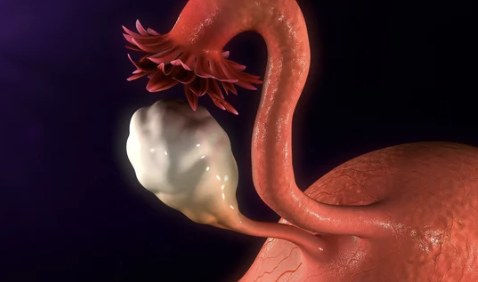

자궁근종 수술은 여성들 사이에서 흔히 발생하는 질병으로, 자궁근종이 크거나 증상이 심각할 때 필요한 치료 방법 중 하나입니다. 자궁근종 수술비용은 수술 방법, 병원의 지역, 의료보험 여부 등 여러 요소에 따라 다양하게 결정됩니다. 대체로 수술비용은 안전하고 전문적인 의료진과 시설을 이용할수록 높아질 수 있습니다. 자궁근종 수술비용에 대해 정확히 알아보고 싶다면, 자세한 정보를 확인해보세요. 정확하게 알아보도록 할게요. 오늘은 자궁근종 수술비용 및 수술후 회복기간(2024)에 대해 알려드리겠습니다.

자궁근종 수술은 여러 가지 방법으로 진행될 수 있으며, 수술 방법에 따라 비용이 달라질 수 있습니다. 일반적으로 가장 일반적인 수술 방법은 자궁근종 절제술인데, 이 경우 자궁 전체 또는 일부를 제거하여 근종을 제거합니다. 이외에도 자궁근종 동결술, 자궁근종 유방술 등의 다양한 수술 방법이 있을 수 있습니다.

자궁근종은 여성의 자궁에 발생하는 비악성 종양으로, 그 치료를 위한 수술은 다양한 방법과 비용이 수반됩니다. 수술 방법과 병원의 종류, 그리고 환자의 개별 상황에 따라 비용은 크게 달라질 수 있으며, 평균적으로는 100만원에서 300만원 사이로 알려져 있습니다. 이러한 비용은 종양의 크기, 위치, 그리고 수술에 필요한 기술적 복잡성에 따라 변동될 수 있습니다. 환자들은 자신의 상태와 필요에 가장 적합한 치료 방법을 선택함으로써, 경제적 부담을 최소화하고 건강을 회복하는 데 집중할 수 있습니다. 이 글은 자궁근종 수술비용의 평균적인 범위와 그 결정 요인들에 대해 설명합니다.